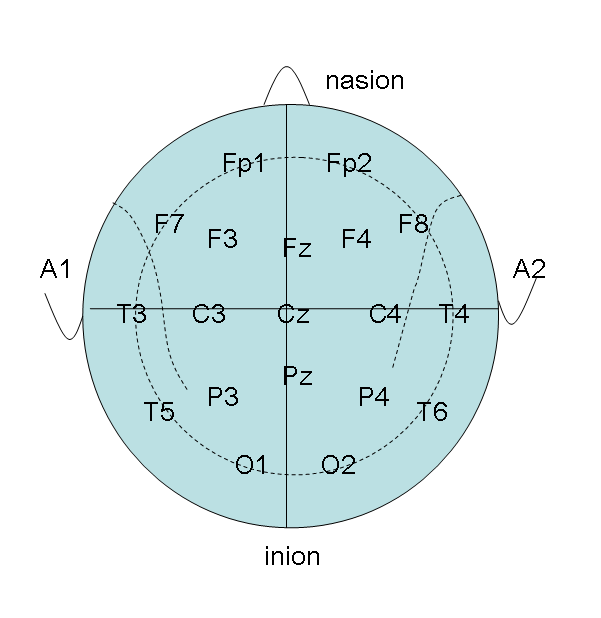

Positionen zur EEG Ableitung

|

|

|---|---|

|